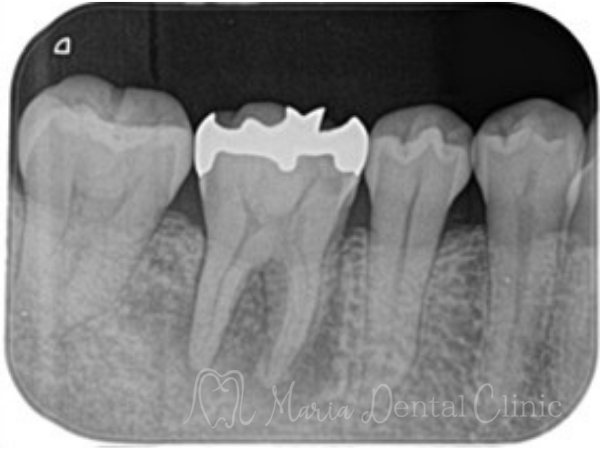

画像2の赤丸部分には被せ物直下に黒く写る黒い影は2次う蝕(2次カリエス)を強く疑うレントゲン写真でした。

マイクロスコープで治療を開始した際に同部位を確認すると、歯科充填材料の下に広がる虫歯を確認し、通法通りのコンセプトに基づき精密根管治療を施しました。